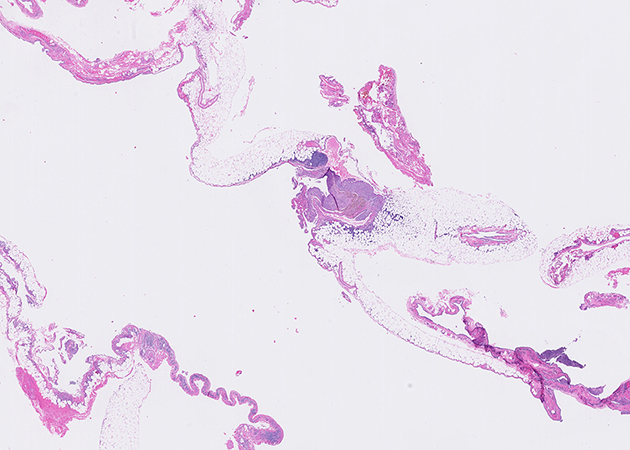

Representative H&E histological images of the pleurectomy specimen are shown in Figures 2 to 4 (1X and 20X magnification) and immunohistochemical stains for CD10 and estrogen receptor performed on the area of Figure 4 are presented in Figures 5 and 6, respectively. The diaphragmatic pedunculated polyp was composed of fibroadipose tissue with multifocal nodules with similar histological features as Figure 4 (not shown).

Low-power histological examination of the pleurectomy specimen (Figure 2) reveals fragments of fibro-adipose tissue covered by a layer of mesothelial cells with focal reactive proliferations (Figure 3). The fragments contain scattered, more densely cellular nodules. Examination at higher magnification reveals the nodules are composed of densely packed small round to ovoid cells with thin-walled capillaries and extravasated red blood cells. Hemosiderin-laden macrophages are evident (Figure 4). Immunohistochemistry confirmed the round cells were positive for CD10 and estrogen receptor (Figures 5 and 6), consistent with endometrial stromal cells and supporting the diagnosis of thoracic endometriosis. Endometrial glands were not seen. The diaphragmatic pedunculated polyp was similarly diagnosed as an endometriosis implant (Question 1).